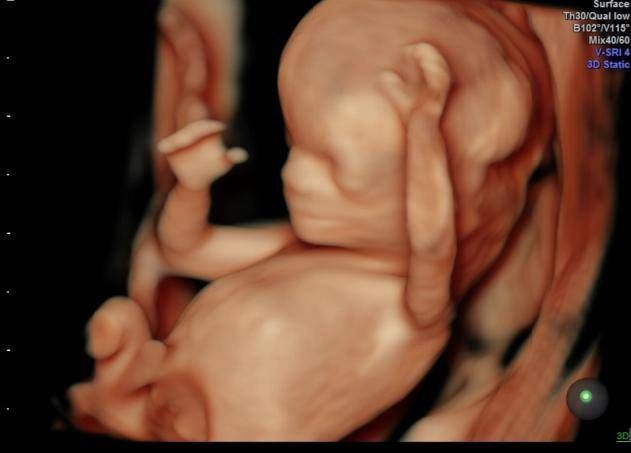

孕期产检,相信不少孕妈妈都很期待四维排畸这一项了,四维彩超排畸检查有不少准妈妈也想带着准爸爸进去,一同分享这其中的喜悦。

【为什么有些医院做四维彩超不让家属陪同这些原因,大家有权知道】小茹怀孕24周左右的时候,身边朋友提醒她这个时候需要做四维大排畸了,不仅能知道胎宝宝发育状况,还可以提前看到宝宝的长相。